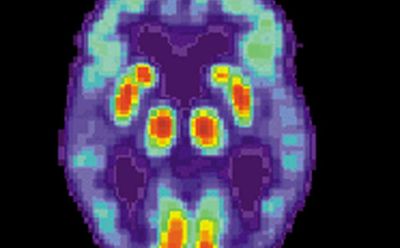

脑缺血及再灌注(MCAO)模型/动物实验